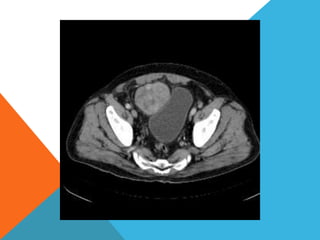

El paciente presentó síntomas de sangrado digestivo y pérdida de peso. Exámenes revelaron gastritis crónica asociada a H. pylori. Un tumor fue descubierto en una colonoscopia normal. La cirugía removió un tumor fibroide solitario, una rara neoplasia mesenquimal que usualmente crece lento y tiene bajo potencial de malignidad. El pronóstico después de la remoción quirúrgica es generalmente bueno.